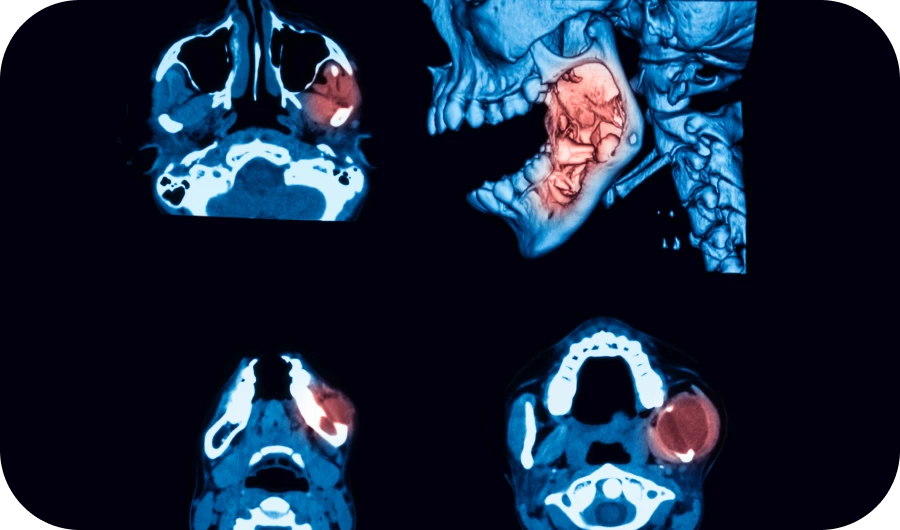

Découvrez les principales affections bucco-dentaires : parodontite, récession gingivale, dents de sagesse, kystes et abcès dentaires. À travers des contenus clairs et illustrés, nous vous expliquons leurs causes, symptômes et options de traitement. Mieux comprendre ces pathologies, c’est mieux prévenir et soigner.